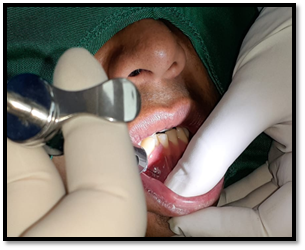

Anestesia: Se colocó la anestesia bucal localizada: 3 cartuchos 1.8 ml de lidocaína al 2% con epinefrina 1:80000 ppm. Se realizó técnica troncular: Nervio dentario inferior, nervio bucal, nervio lingual y al nervio mentoniano.

Imagen 5. Anestesia troncular al mandíbular y al mentoniano.